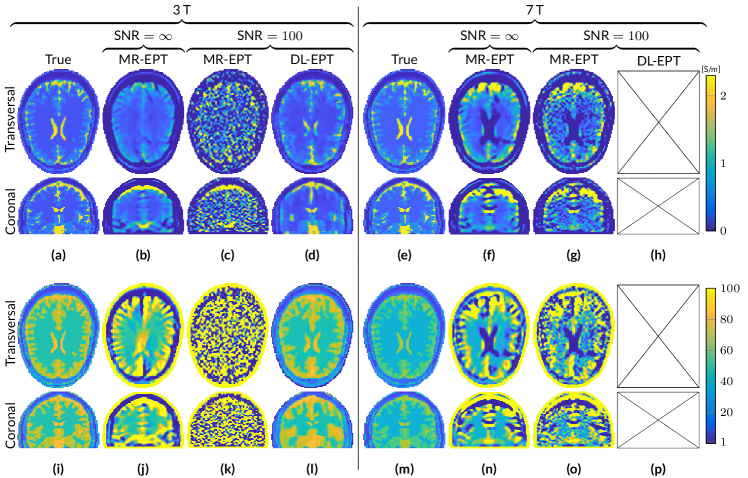

Figure 2: Reconstructed EP maps from different EPT reconstruction approaches for the male head model at 3 T and 7 T based on B^1+superscriptsubscript^𝐵1\hat{B}_{1}^{+} data with an SNR of 100. Conductivity (a-h) and permittivity (i-p).

Figure 2 shows reconstruction results when Gaussian noise is present in the B^1+superscriptsubscript^𝐵1\hat{B}_{1}^{+} data (SNR=100)SNR100(\text{SNR}=100). The introduction of noise results in non-significant differences for H-CSI reconstructions both at 3 T and 7 T. This is in contrast to MR-CSI, whose initialization maps, i.e. EP maps obtained from standard Helmholtz MR-EPT reconstructions, are extremely sensitive to noise (see Figure S1), thus leading to noise corrupted MR-CSI reconstructions, both at 3 T and 7 T. DL-CSI reconstructions are minimally affected by noise, which leads to slightly higher standard deviations in permittivity reconstructions for DL-CSI compared to DL-EPT (See Table S1).

In the supplementary material Table S1, the mean and standard deviation values are reported for EP reconstructions in the WM, GM and CSF from noiseless and noisy data for all the aforementioned methods (MR-EPT, DL-EPT, H-CSI, MR-CSI and DL-CSI) as a proxy of accuracy and precision.